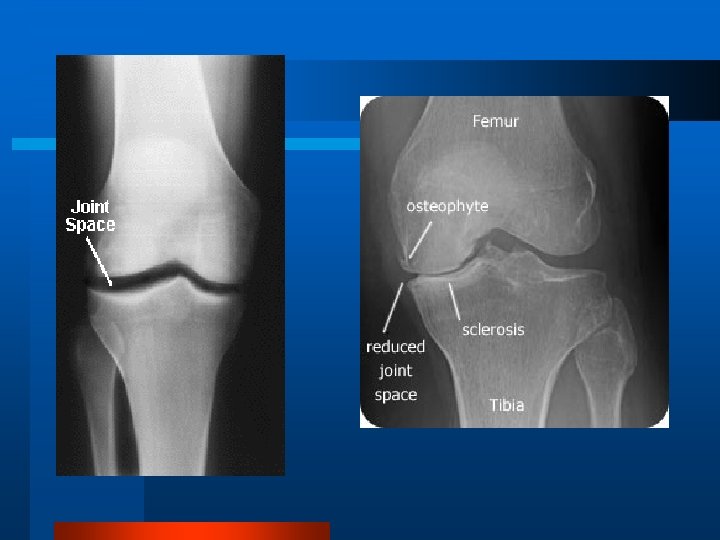

Examenul radiologic l Radiografia simplă este cel mai util mijloc imagistic în artroză, atât pentru diagnostic, cât şi pentru urmărirea evoluţiei. Aspectul l Îngustarea spaţiului articular l Scleroză subcondrală l Osteofitoză marginală l Pseudochisturi sau geode

Gradarea Kellgren-Lawrence 0: Normal I: Osteofite posibile şi posibil pensarea spaţiului articular II: Osteofite definite şi posibil pensarea spaţiului articular III: Osteofite moderate multiple, pensarea definită a spaţiului articular, scleroză şi posibil deformare a conturului osos IV: Osteofite mari, pensarea marcată a spaţiului articular, scleroză severă, şi deformare definită a conturului osos